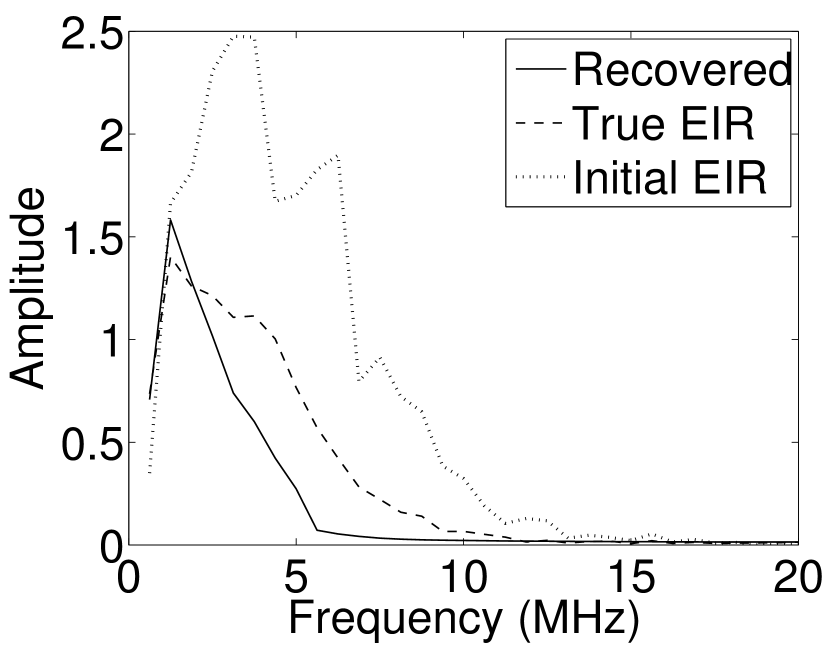

Each element in a real-world transducer array possesses its own EIR. In practice, the differences between the EIRs are sometimes neglected and an EIR corresponding to a single element may be used to represent all elements in the array. In some of the studies below, the EIR employed to initialize the VP algorithm (EIR-2 in Figure 1(b)) and the EIR employed to produce the simulated measurements (EIR-1 in Figure 1(b)) were experimentally measured from two different transducer elements in a circular transducer array (see Sec. VI-B). EIR-1 was measured by temporally integrating the PA signal produced by a point source positioned at the focus of the transducer. EIR-2 was measured by use of the method reported in [RNR2011]. In order to investigate the sensitivity of the VP algorithm to the initialization of the EIR, we employed different EIRs obtained by degrading EIR-1 as described later. When solving the sub-problem in Line-2 of Algorithm 1, was initialized as the zero vector. Algorithm 1 was terminated after 500 iterations, since it was observed that the changes in the reconstructed images with more iterations were negligible. When implemented by use of a single core of an Intel Xeon E5-2640 CPU, each iteration required approximately 7s to complete.

The original sharp phantom shown in Figure 1(a) was convolved with a Gaussian blurring kernel to generate a smoothed phantom that possessed smaller relative spatial bandwidths. We employed the sharp and the smoothed phantoms to generate pressure data; the pressure data generated by the sharp phantom had a larger bandwidth than that generated by the smoothed one, as shown in Figure 3.

As shown in Figure 6, when the error in the EIR was small (e.g., as with the EIR in Figure 6(a)), images were reconstructed with high accuracy using the VP algorithm. When the perturbations in the EIR were stronger (e.g, as in Figure 6(c)), artifacts and distortions in the reconstructed images were still significantly reduced by use of the VP algorithm; however, larger values of the regularization parameters had to be applied. When as in the initial EIR in Figure 6(e), no improvement was observed in the image reconstructed by use of the VP algorithm.

Figure 7(a) reveals that use of the inaccurate EIR in the conventional iterative method created strong artifacts and distortions. Figures 7(b) confirms that the artifacts and distortions were significantly mitigated when the VP method was employed. Image profiles for both cases are shown in Figures 7(c). The overall accuracy of the recovered EIR, shown in Figure 7(d) and 7(e), was improved, but it contained spurious oscillations.

Images reconstructed by use of the VP algorithm with different values of the regularization parameter values are shown in Figure 8. The recovered EIRs and their corresponding Fourier spectra are shown in Figures 9 and 10, respectively. The RMSE values are computed and displayed together with the corresponding images. As expected, the images reconstructed with smaller values of contain higher noise levels, while images using larger possess a reduced noise level. However, larger values of also caused artifacts in the reconstructed images. The same observation can be made for the effect of the regularization parameter on the recovered EIR. One also observes that the reconstructed images and EIRs depend continuously on the regularization parameters and , i.e. small changes in the regularization parameters cause minor changes in the reconstructed images and EIRs.